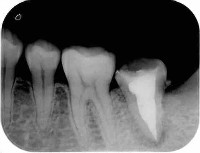

根管の中に入れた最終的なお薬が根の先までしっかり入って、歯の間のコントラストがはっきりしてます。

根管の細菌に感染した歯質をしっかりとって、最終的なお薬で隙間なく埋める事で細菌が感染増殖するのを防ぎます

根管と歯のコントラストがはっきり見えません。

それは違う角度から見ると最終的なお薬が緊密に入っていないか、感染歯質を取りきれていないからです。

根のお掃除が不十分で、さらに最終的なお薬とのコントラストがはっきりしておらず、隙間だらけです

しっかりと感染歯質をとり、緊密に最終的なお薬をつめているので歯とお薬のコントラストもはっきりしています。